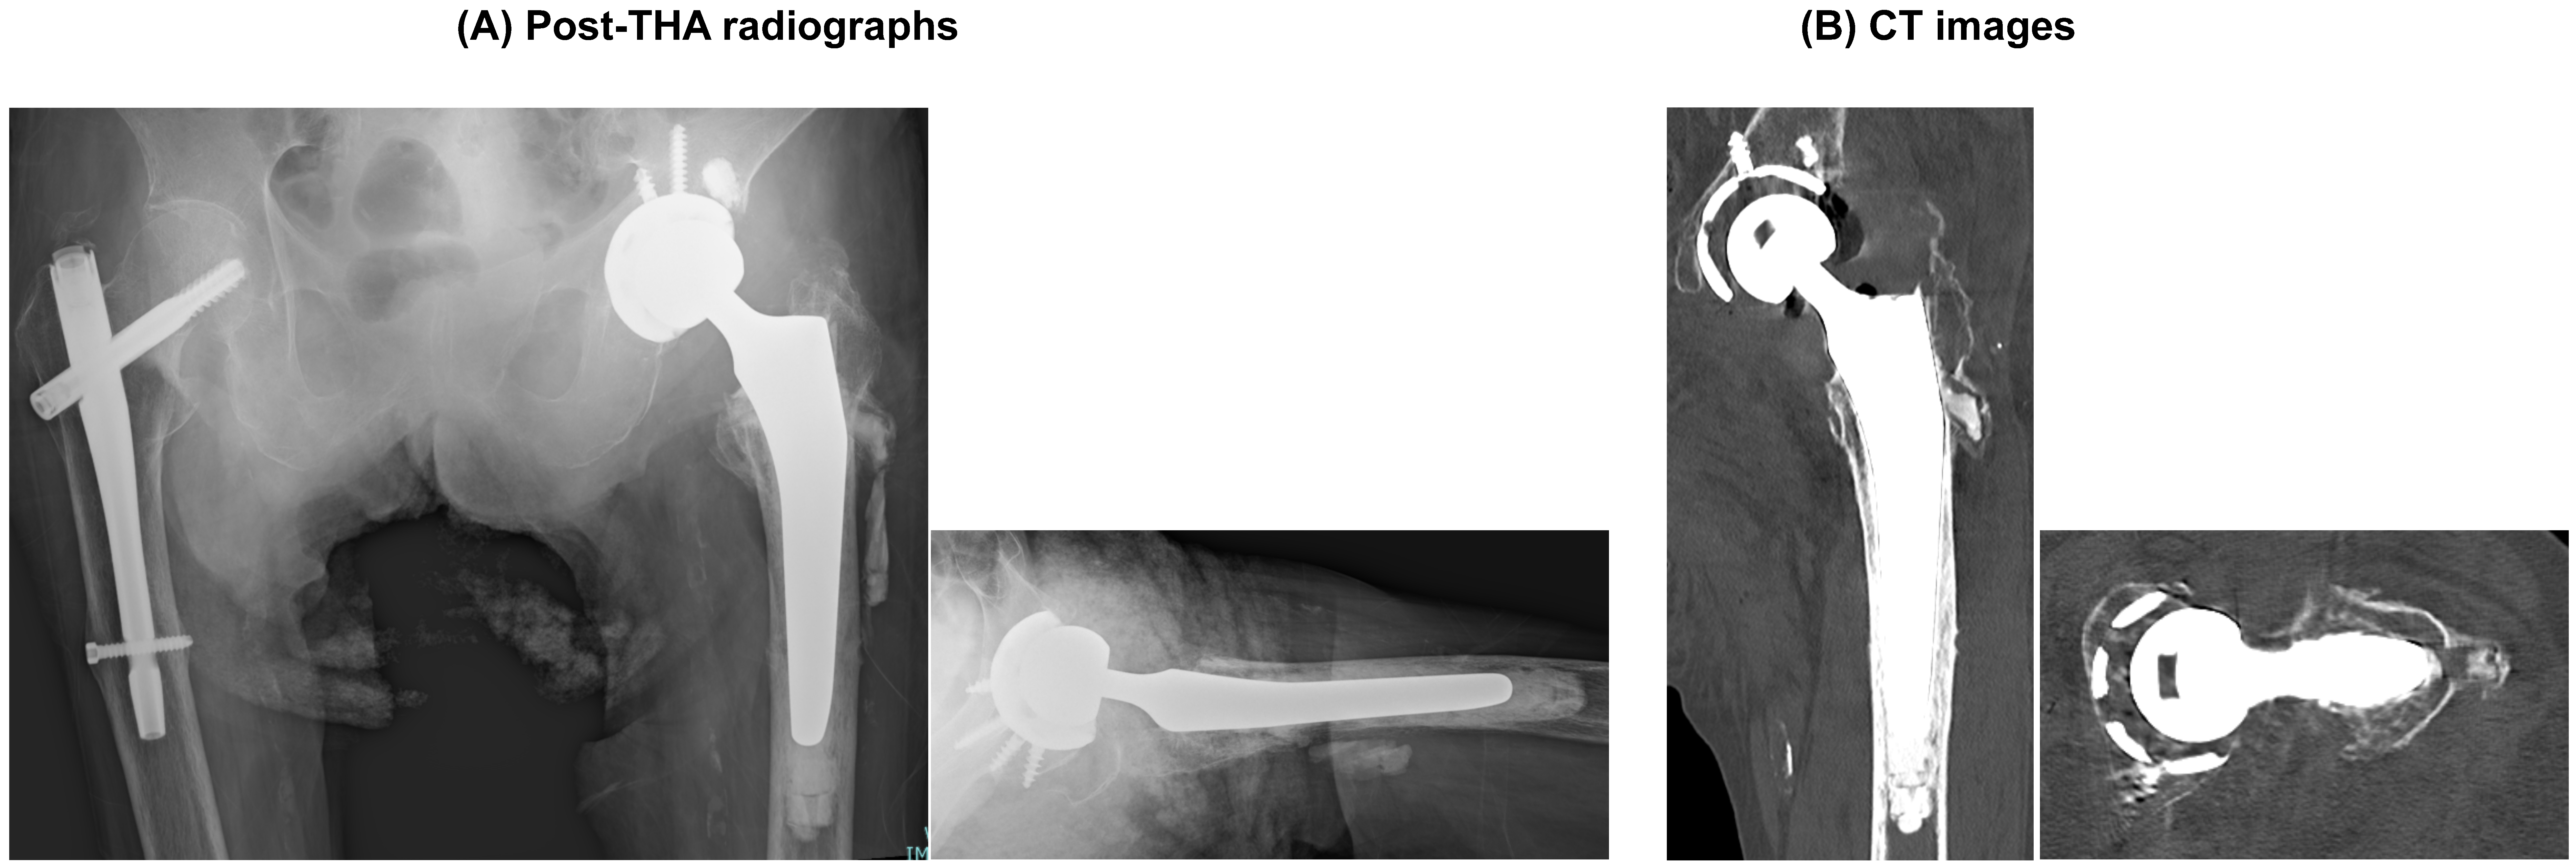

3.5. Salvage Procedure and Outcome

The patient underwent conversion to total hip arthroplasty (THA), and postoperative AP and lateral radiographs confirmed appropriate component positioning (Figure 6). At the latest follow-up, the pain improved and ambulatory function recovered (indoor ambulation with a walking aid), with stable components and no evidence of migration.

Figure 6. Post-THA radiographs. (A) Post-salvage radiographs: AP (left) and lateral (right) views obtained after conversion to total hip arthroplasty, demonstrating the final component position. (B) Representative CT images (coronal reconstruction, left; axial slice, right).